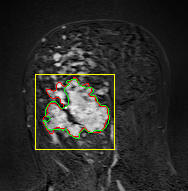

We tested the algorithm by varying the number of markers between and . Fig 2 describes the segmentation results obtained using different numbers of markers. This plot indicates that markers were found to be optimal using this segmentation approach, yielding satisfactory results.

where refers to the ROIs segmented by our algorithm and is tumor area as determined by manual segmentation. Table 1 summarizes the segmentation accuracy achieved using the proposed method for all 106 cases. The average dice coefficient was found to be 0.780.17 and average Jaccard index was 0.670.21. Fig 3 demonstrate four sample segmentation outputs which are overlaid on manual segmentations provided by two radiologists. It can be seen, that the proposed method could accurately segment the lesions with some marginal errors for medium to large tumors. However, for cases comprising disjoint lesions, the method failed to segment all small lesions and in some cases incorrectly labeled healthy tissue as lesions. This is because in some cases there is a high degree of overlap in the intensity distributions of healthy breast tissue and lesions, and the ROI drawn by the radiologist is very large in the case of disjoint lesions, in order to cover the entire area over which multiple lesions are distributed.